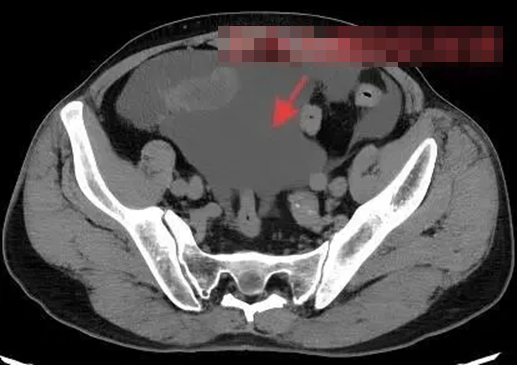

Nước tiểu trong ổ bụng bệnh nhân

Kết quả chụp cắt lớp vi tính (CT) cấp cứu cho thấy trong ổ bụng bệnh nhân có một lượng lớn dịch bất thường. Các bác sĩ nhanh chóng hội chẩn và nghi ngờ cao tình trạng vỡ bàng quang. Sau khi được khoa Tiết niệu đánh giá, bệnh nhân được chẩn đoán mắc vỡ bàng quang trong phúc mạc, một trong những thể vỡ bàng quang nguy hiểm nhất.